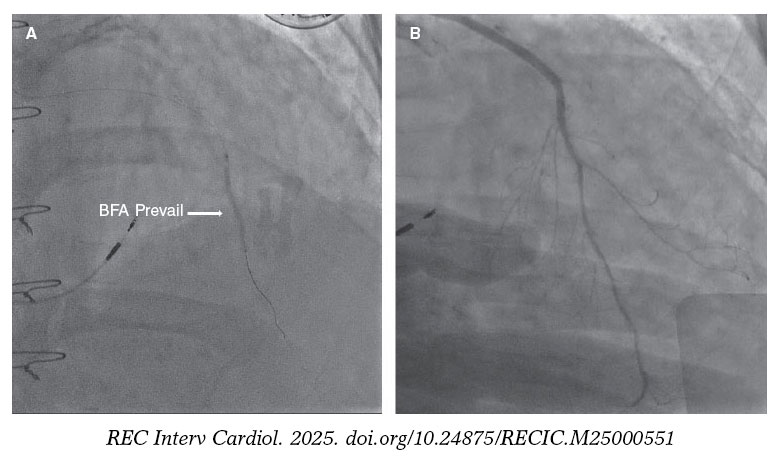

Posteriormente, se avanzó un dispositivo de aspiración Thrombuster II (Kaneka Corp., Japón) hasta el segmento medio de la AMII. La inyección de contraste mostró una oclusión en la anastomosis AMII–DA (figura 1F, flecha). Aunque la trombectomía restableció el flujo, persistía una estenosis grave en el sitio de la anastomosis. Se realizó angioplastia con balón y posteriormente se implantó un balón farmacoactivo (BFA) Prevail de 2,0 × 30 mm (Medtronic, Estados Unidos) a través del injerto y la DA nativa (figura 2A, flecha). La angiografía final mostró un excelente flujo distal (figura 2B; vídeo 2 del material adicional), resolución del segmento ST y mejoría hemodinámica.

Figura 2.